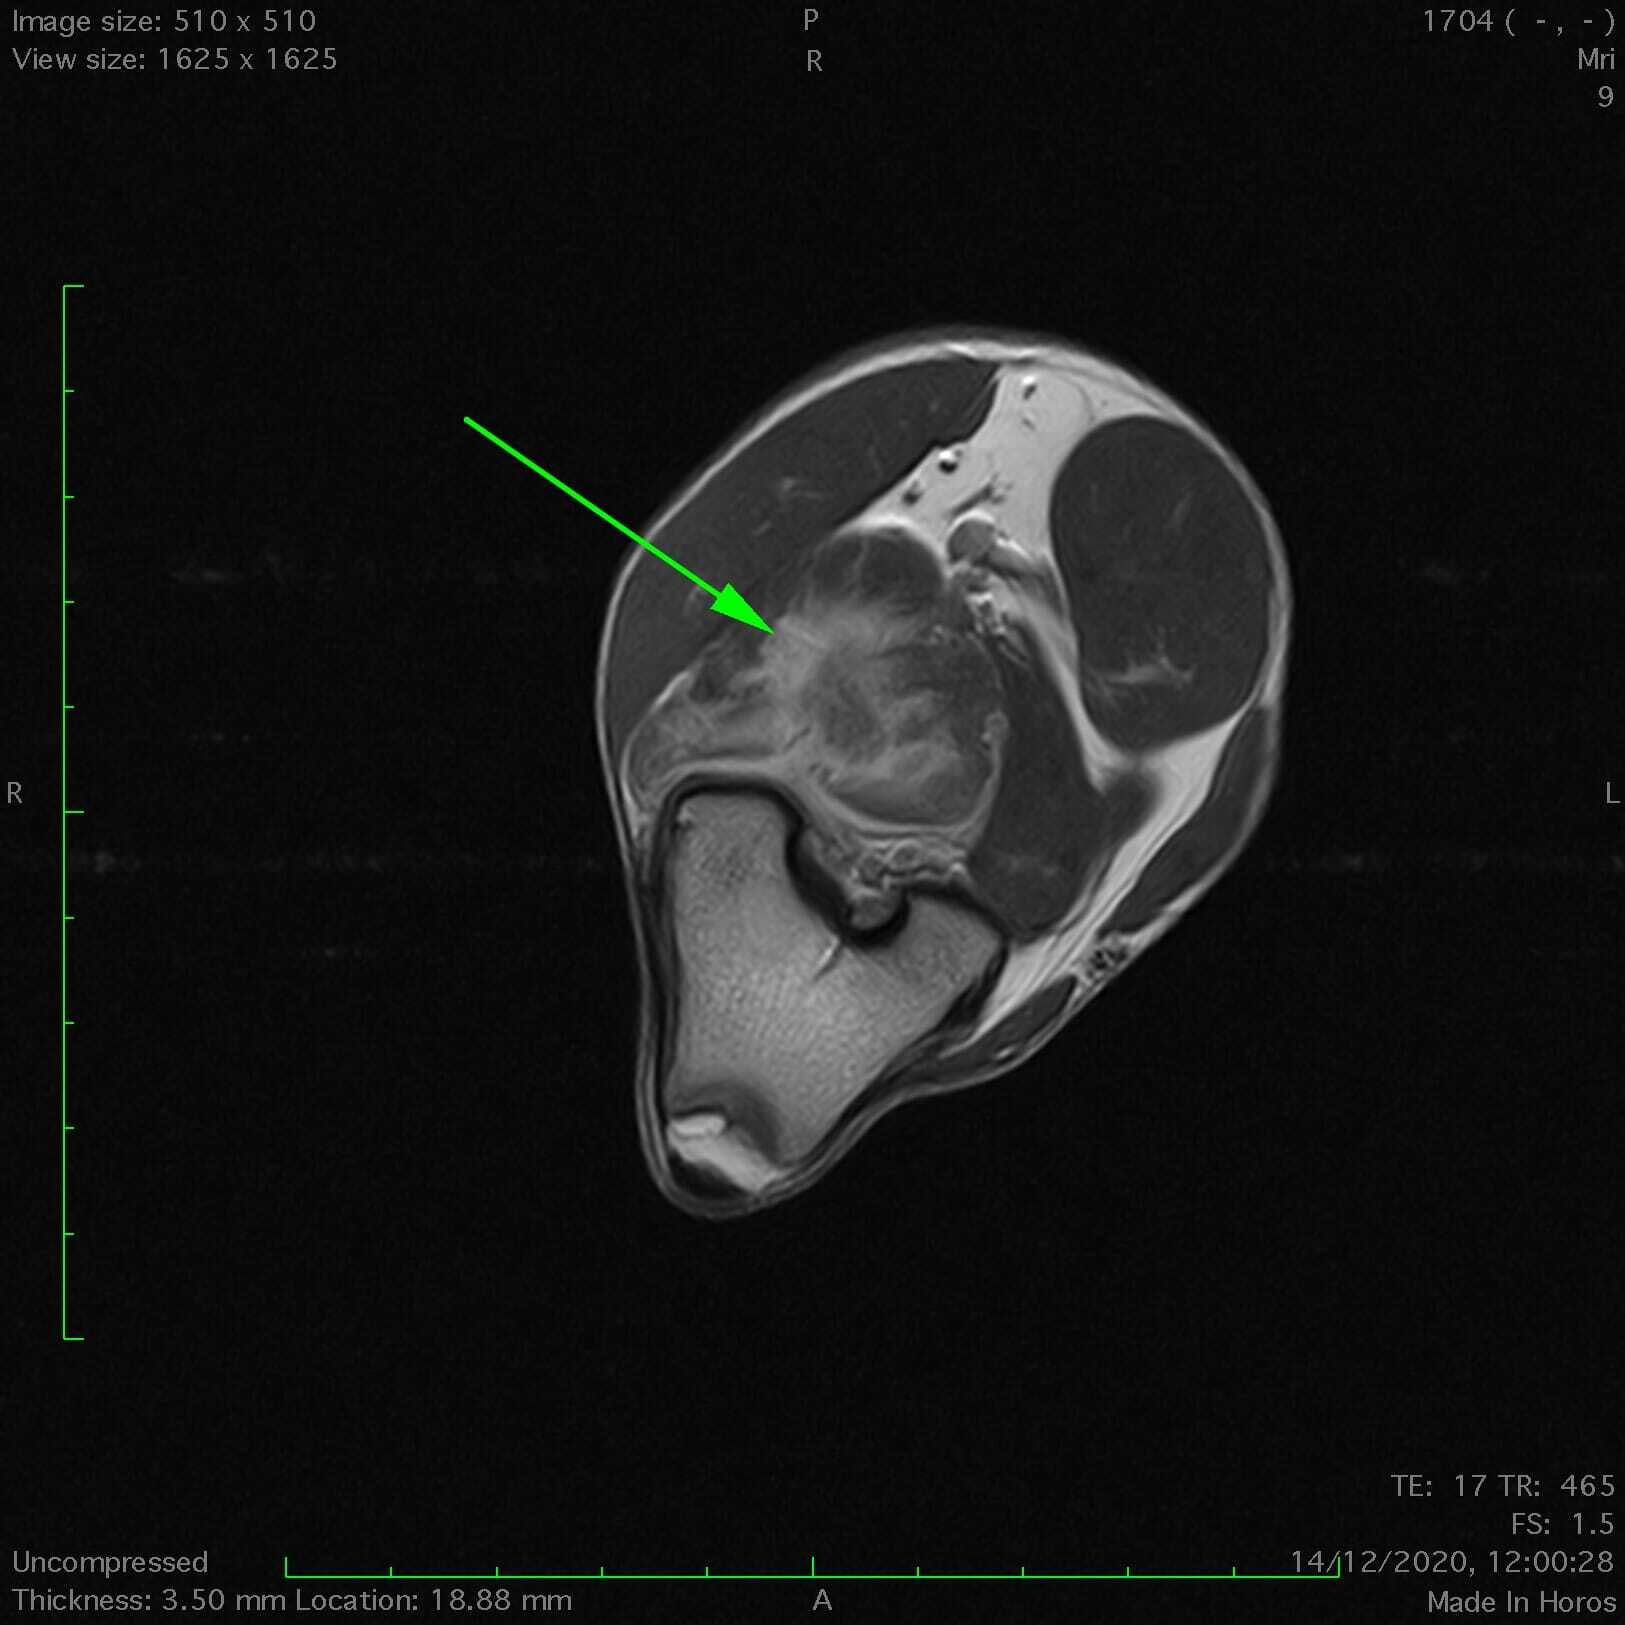

La modalité de référence pour l'évaluation des lésions des tissus mous est l'imagerie par résonance magnétique (IRM), qui est pratiquée couramment chez l'homme. Elle devient de plus en plus courante chez les animaux et continuera à l'être au fur et à mesure que l'expérience dans ce domaine s'accroîtra (Figure 4).